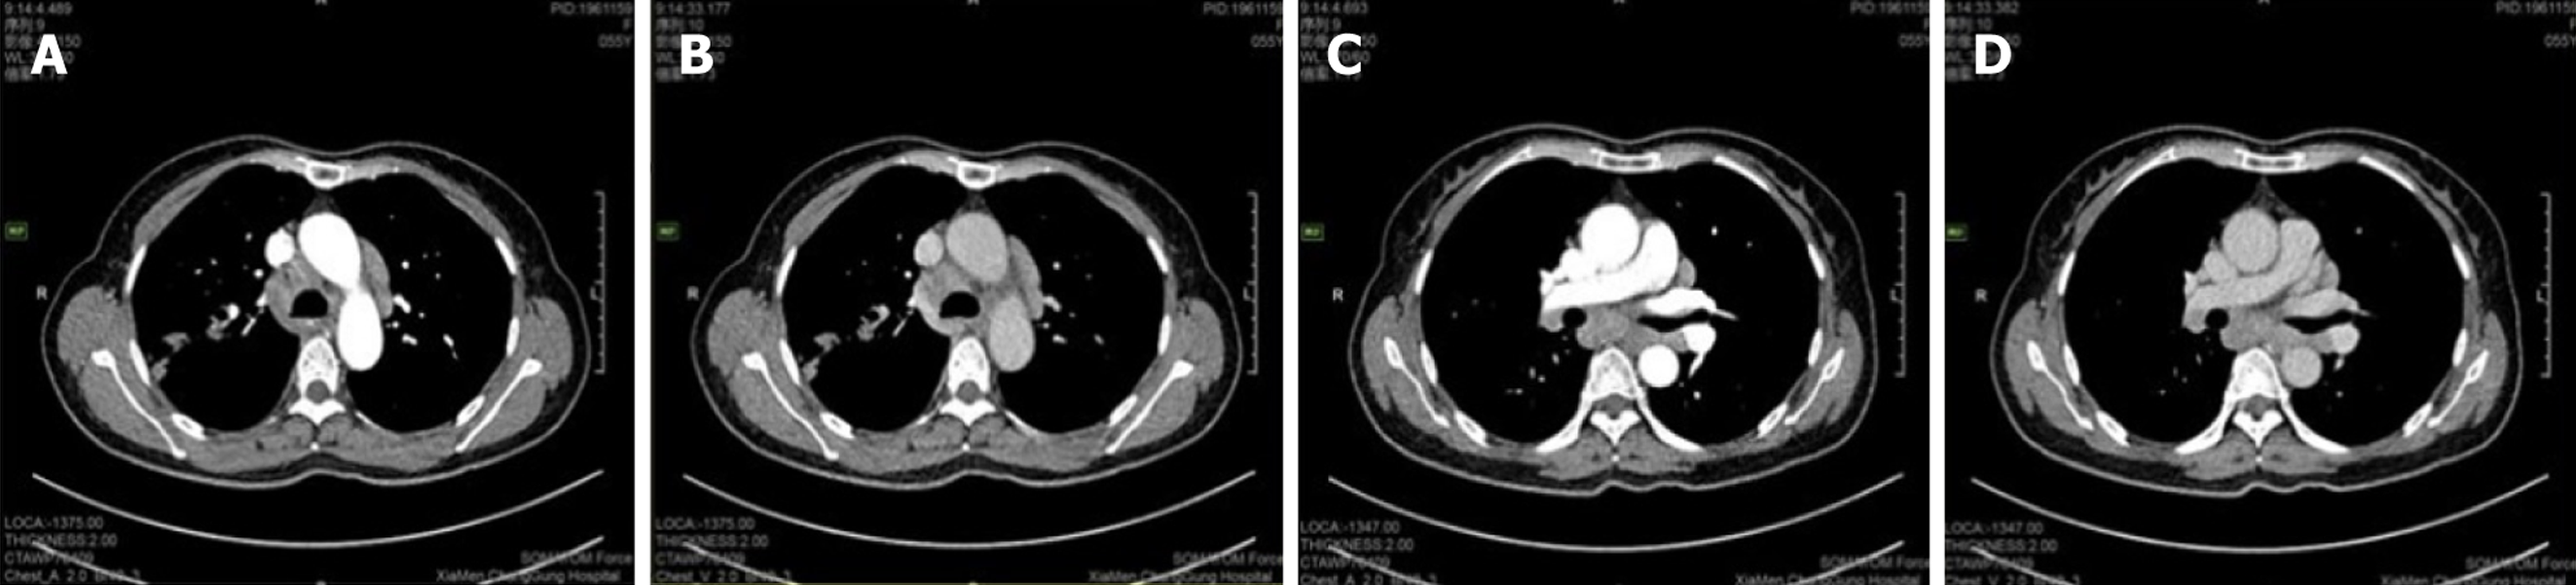

Case 1: A routine chest CT 20 days earlier had revealed a right lung shadow. Subsequent contrast-enhanced chest CT (June 6, 2024) at an external hospital demonstrated a hypervascular right hilar mass with surrounding obstructive pneumonia, scattered enlarged mediastinal lymph nodes, and right pleural effusion. PET-CT suggested malignancy in the right upper lobe with possible pleural involvement, lymphangitic carcinomatosis, and metastases to bilateral hilar/mediastinal lymph nodes (June 17, 2024; Figure 3). In addition, multiple subpleural lung nodules with low metabolic activity were observed. A repeat contrast-enhanced chest CT on June 28, 2024, confirmed a 2.7 cm × 2.0 cm irregular, heterogeneous mass in the right upper lobe, accompanied by obstructive pneumonia and enlarged right hilar and medi

Classic thoracic imaging features include bilateral hilar/mediastinal lymphadenopathy with pulmonary infiltrates. However, atypical radiological findings - as seen in both our cases - pose diagnostic challenges. Case 1 presented with a right upper lobe mass and paratracheal lymphadenopathy mimicking lung cancer with metastases, while case 2 exhibited multiregional hypermetabolic lymphadenopathy and thrombocytopenia, initially suggestive of lymphoma. These scenarios underscore the necessity of integrating clinical, radiological, and histopathological data for accurate diagnosis. Bronchoscopy with bronchoalveolar lavage lymphocyte subset analysis (increased CD4/CD8 ratio) and mediastinal lymph node sampling are pivotal in such ambiguous cases.